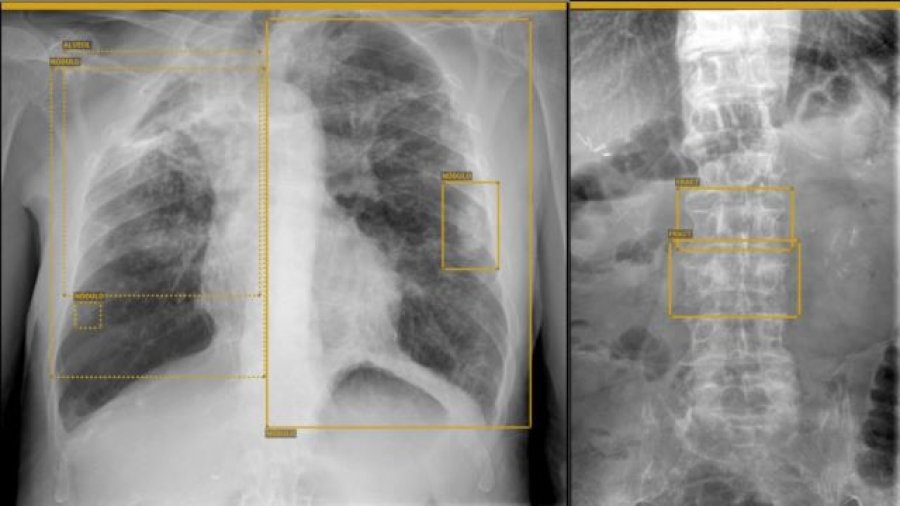

El Hospital Universitario Nuestra Señora de Candelaria, centro adscrito a la Consejería de Sanidad del Gobierno de Canarias, ha implantado en el servicio de Radiología un proyecto piloto, en coordinación con la empresa GLEAMER, mediante el cual se empleará la inteligencia artificial para mejorar la detección de lesiones.

Entre ellas se podrán valorar lesiones óseas traumáticas y tumorales, además de patologías en el entorno de la ortopedia y la rehabilitación (dismetrías o escoliosis…) y la radiología de tórax que se realiza en el ámbito de Urgencias (neumonías, tumores, derrames, etc.).

Con su implantación se consigue que sea la IA la que realice unos cálculos necesarios para conocer los grados de escoliosis o diferencia de altura en la cadera del paciente, entre otros aspectos. Esto lo suele llevar a cabo el rehabilitador, cuyo tiempo puede ahora invertir en una mayor atención en el paciente.

Asimismo, se optimiza el tiempo de respuesta del especialista y aumenta la confianza y la seguridad de la prueba diagnóstica, ya que la IA ayuda al profesional que está realizándola, proporcionando una doble visión de la prueba y localizando con mayor probabilidad una patología, aumentando la calidad diagnóstica del paciente.